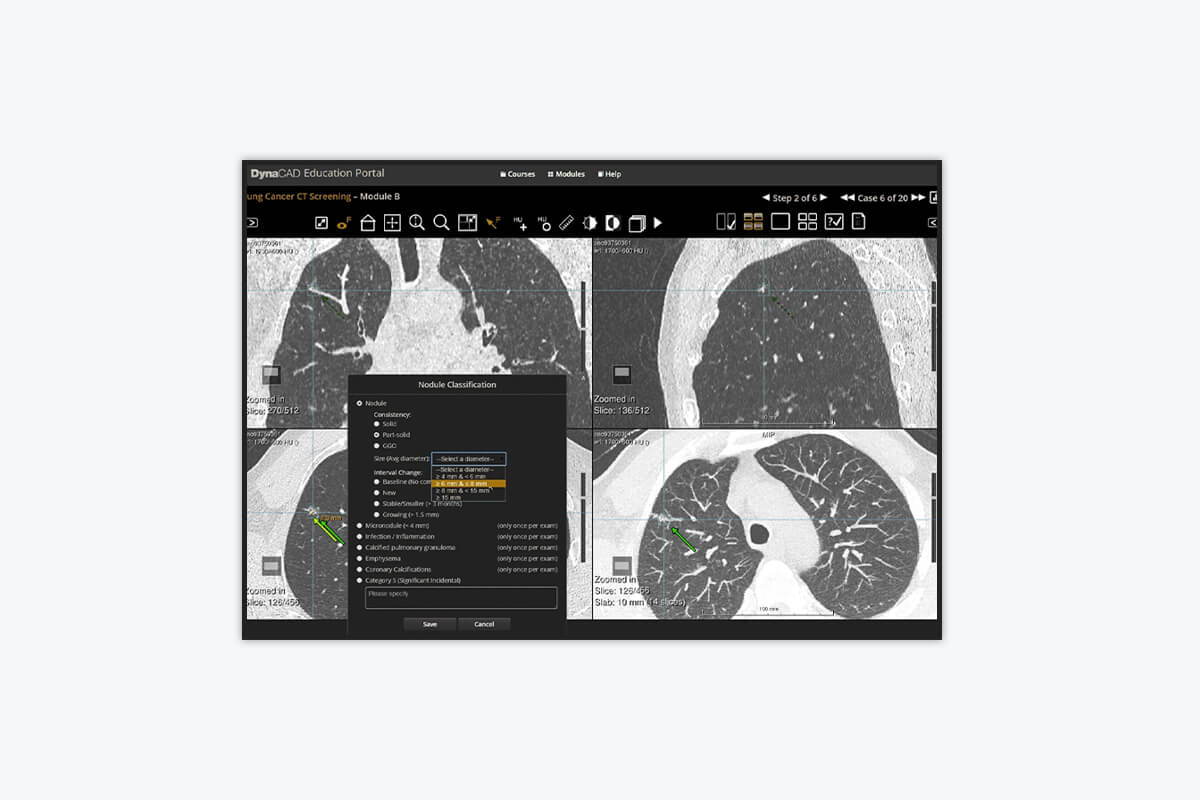

Advanced Lung Cancer Screening

You may qualify for low dose CT (LDCT) lung cancer screening if you’re 55 to 77 years old, have no symptoms of lung cancer, currently smoke (or quit within the past 15 years), and have a 30-year history of heavy smoking. If you think you qualify or have a prescription from your doctor for LDCT lung screening, please call to speak with a scheduler.

Technology Spotlight

Adventist Health Glendale has long been at the forefront of offering programs and cutting-edge technology for early detection of a wide range of conditions. The adoption of DynaLync and DynaCAD Lung provides critical tools to aid with the identification, tracking, and management of relevant information to help physicians reach a quick and definitive diagnosis. We utilize low dose CT (LDCT) lung screening, which is quick and easy and results in a minimal amount of radiation exposure. We are determined to raise awareness and improve access to this testing for all people at high risk. Therefore, we are currently offering LDCT lung screening to individuals who meet established high-risk criteria.